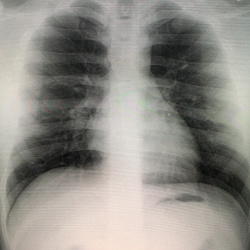

Мужчина, 42 лет, поступил с жалобами на слабость, головную боль, кашель, одышку, считает себя больным в течении 3 дней, когда появились эти жалобы, самостолятельно принимал противовоирусные...